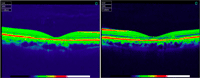

La tomografía de coherencia óptica detectó un adelgazamiento foveal bilateral más pronunciado en el ojo derecho (

Figura 2). Se realizó una angiografía con fluoresceína que objetivó silencio coroideo en todas las fases del angiograma y la aparición de múltiples focos hiperfluorescentes alrededor de la fóvea en ambos ojos (

Figura 2. Tomografía de coherencia óptica. Atrofia foveal bilateral más pronunciada en el ojo derecho (imagen de la izquierda).